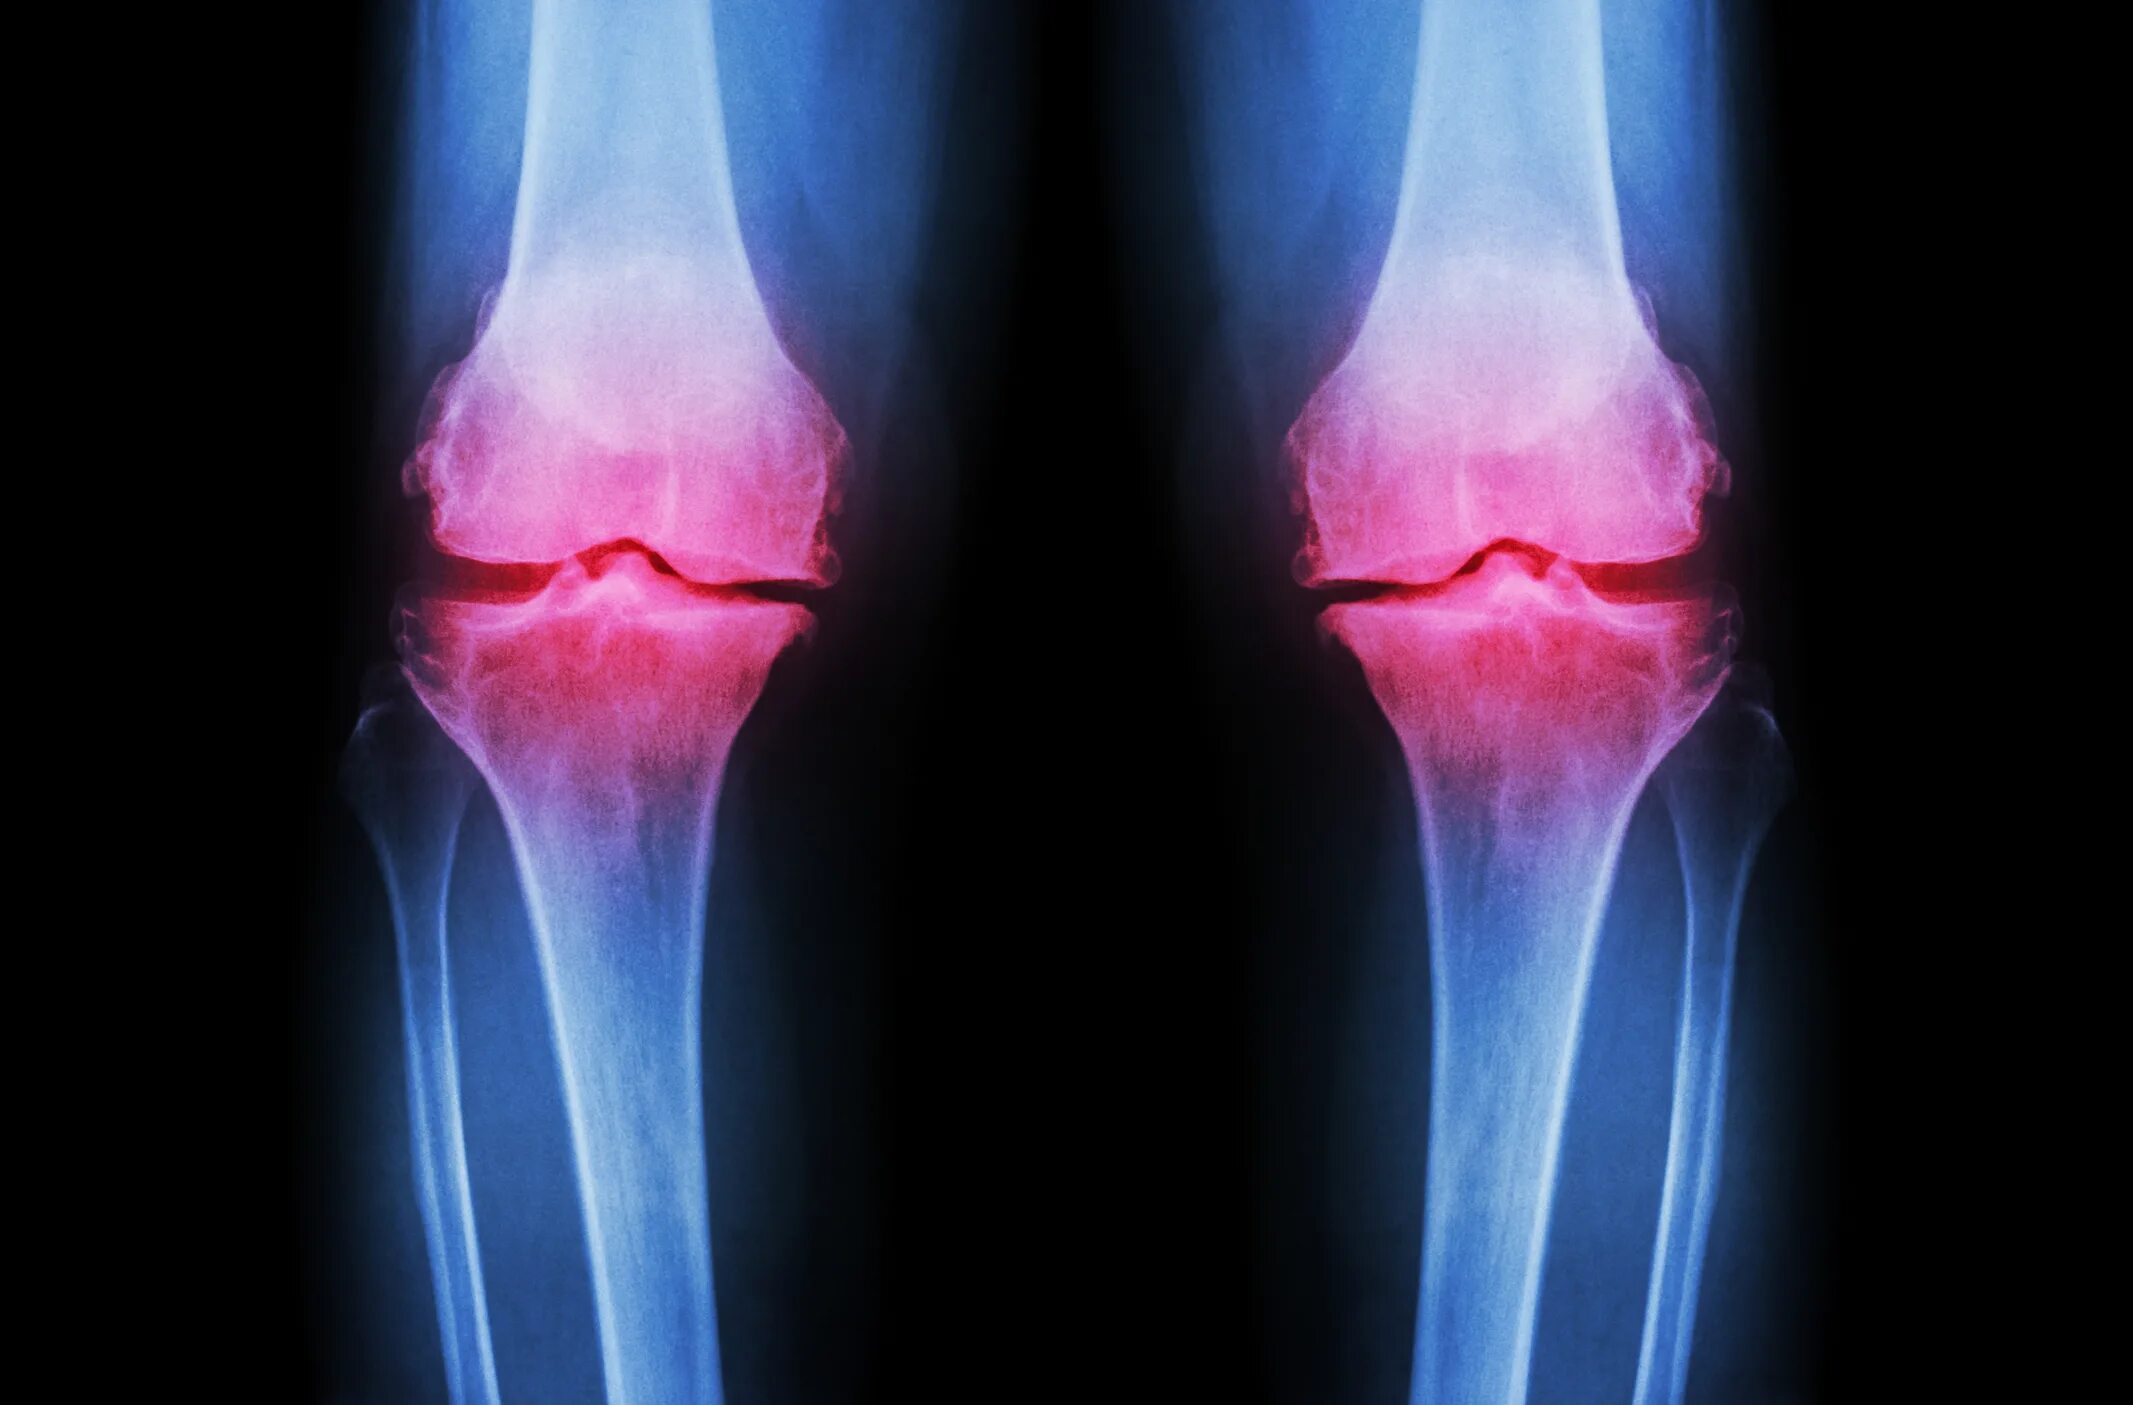

Остеоартрит 2025